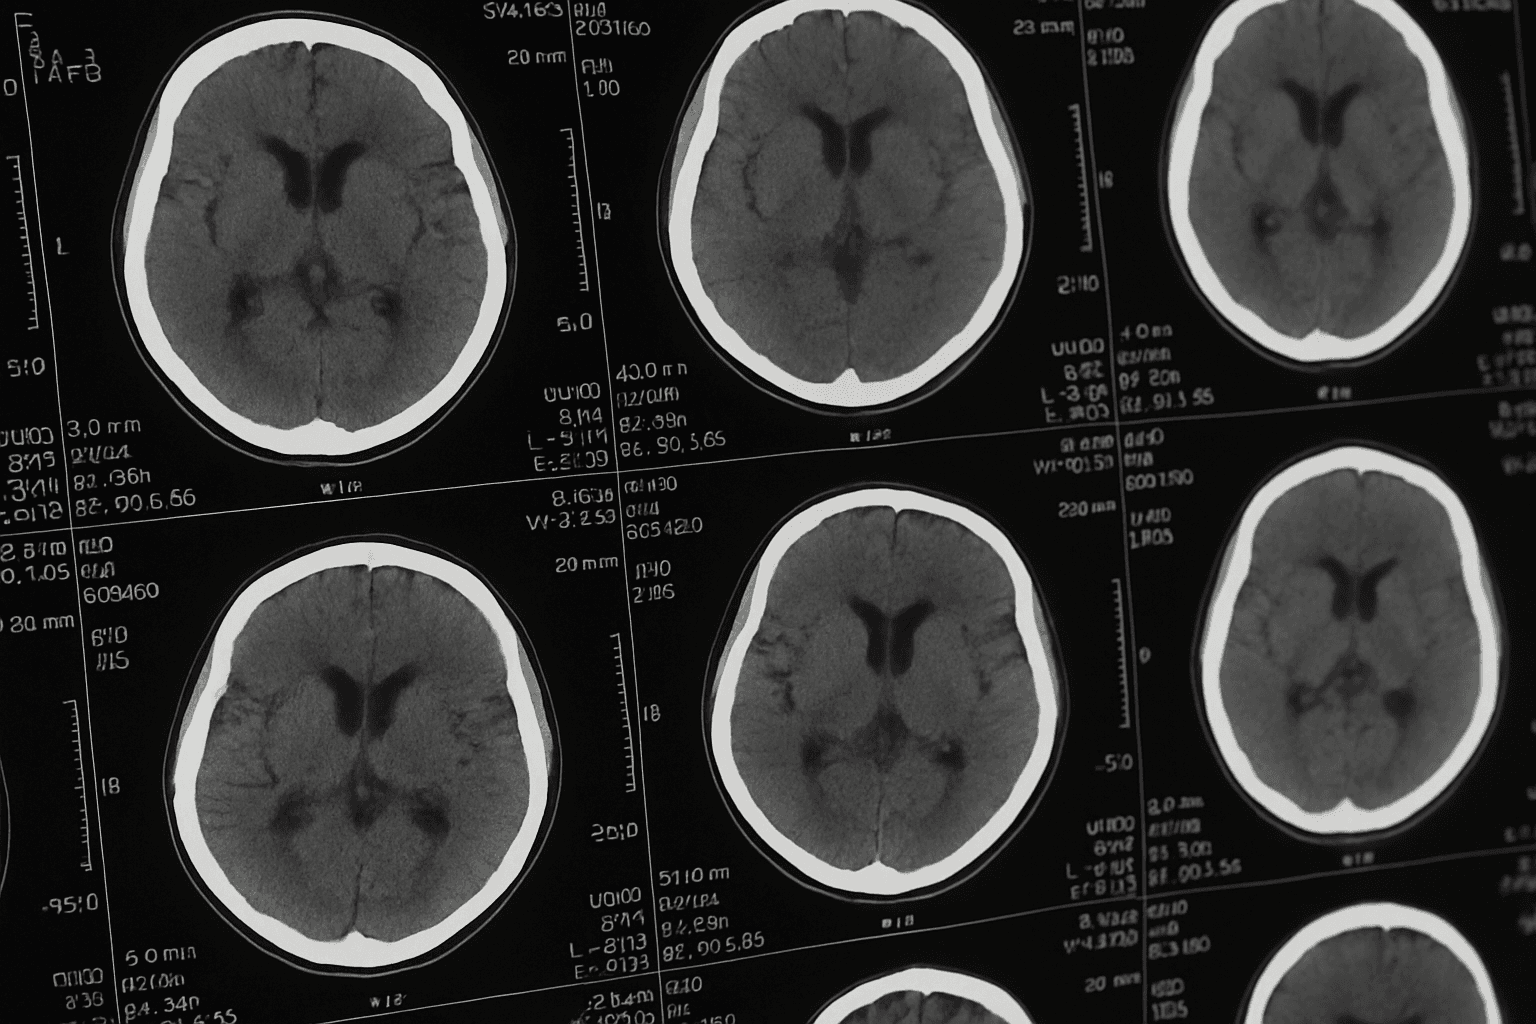

La Malattia di Parkinson è una patologia neurodegenerativa progressiva che colpisce il sistema nervoso centrale, in particolare le cellule che producono dopamina – una sostanza chiave per il controllo dei movimenti, dell’equilibrio e di alcune funzioni cognitive ed emotive. Sebbene sia nota per i tremori e la rigidità muscolare, il Parkinson è molto più di una semplice malattia del movimento. Col tempo può manifestarsi con lentezza nei movimenti (bradicinesia), instabilità posturale, difficoltà nell’articolazione della parola, alterazioni dell’umore, disturbi del sonno e del pensiero. L’esordio è spesso subdolo e i sintomi si evolvono in modo diverso da persona a persona, rendendo ogni caso unico.

Le origini del Parkinson non sono ancora del tutto chiare. Si ritiene che fattori genetici, ambientali e biologici contribuiscano all’accumulo di proteine anomale (corpi di Lewy) nelle cellule nervose e alla morte progressiva dei neuroni dopaminergici. La carenza di dopamina altera profondamente i circuiti cerebrali che regolano movimento, motivazione e attenzione. Col progredire della malattia, anche altre aree cerebrali vengono coinvolte, dando origine ai sintomi non motori che spesso precedono o accompagnano la fase clinica più evidente.